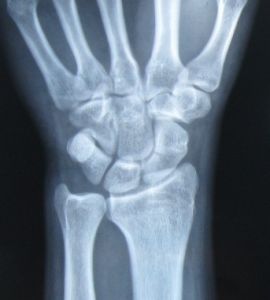

1.2診斷依據所有的病例除具有Colle's骨折的特徵外,均有 鼻煙窩凹陷消失和壓痛,腕舟骨結節壓痛,第1、2掌骨縱軸叩擊痛及腕關節橈偏背伸活動受限和疼痛。腕關節正側斜位X線片除見有明顯的 橈骨遠端骨折外,可見腕舟骨有橫穿對側骨皮質的骨折線。